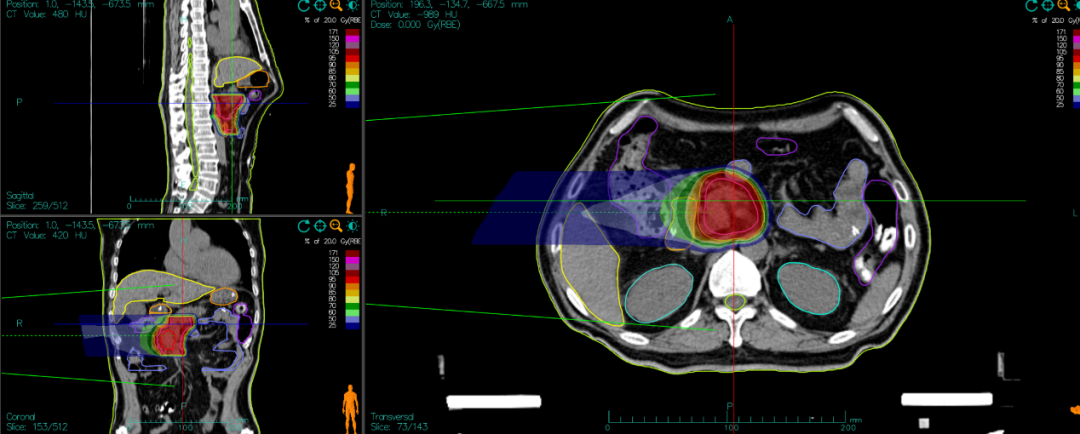

[Carbon Ion Radiotherapy Plan]

- Carbon ion radiotherapy dose:

- PTV 36Gy (RBE)/9 fractions, followed by a reduced-field boost.

- PTV boost 18Gy (RBE)/4 fractions, 4.5Gy (RBE) per fraction.